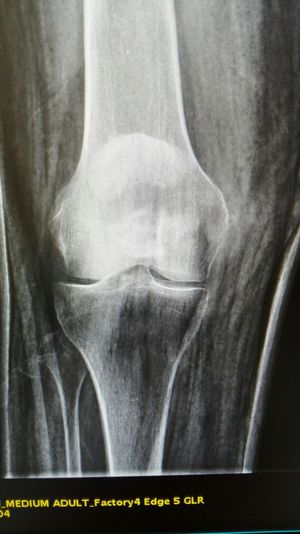

Xray

Fracture

Patella